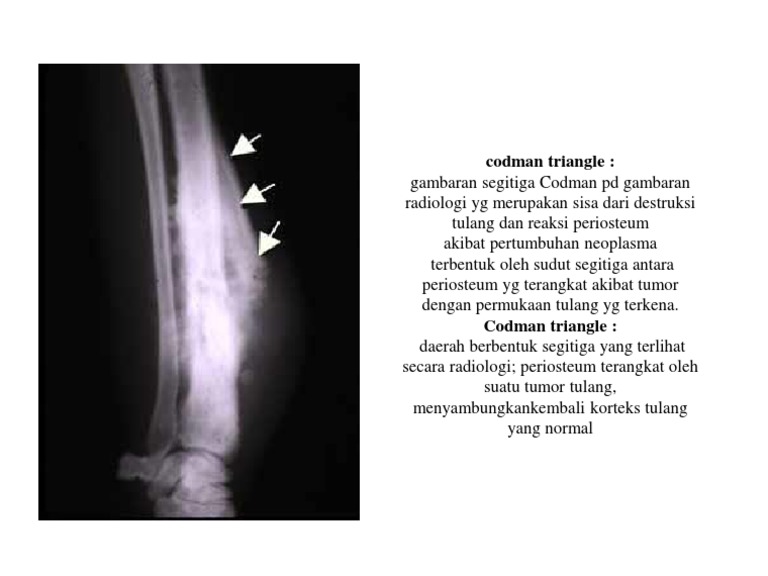

Codman's Triangle: A Radiological Sign of Bone Destruction Due to Tumor ...

Codman triangle - a distinctive triangular form of periosteal reaction ...